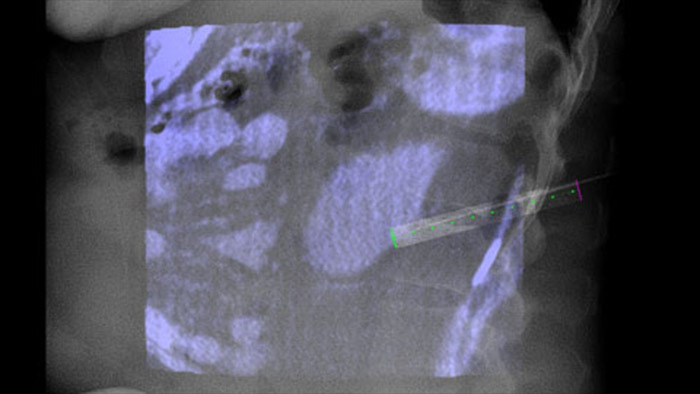

XperGuide proporciona una orientación por imágenes en tiempo real extremadamente preciso de cada aguja a una posición objetivo mediante la superposición de trayectorias preplanificadas con imágenes fluoroscópicas3.

Dual View permite la superposición de una imagen 3D previa al procedimiento (TC/RM/PET-CT) en una CBCT Dual 3D durante procedimiento para visualizar mejor las lesiones y acceder a la entrada crítica para la planificación de la aguja.

La heterogeneidad de la lesión y la falta de notoriedad limitan la calidad de las muestras, así como la viabilidad de las biopsias cuando se realizan mediante ecografía o CT convencional. Con el aumento de la adopción de programas de detección en los pulmones, se han detectado cánceres pulmonares incipientes que se manifiestan como nódulos pequeños con mayor frecuencia que antes. Se observó que el 14.5% de una población seleccionada tenía nódulos ≤10 mm1-2. Nuestra tecnología de navegación guiada por aguja con CBCT aumenta la precisión y permite la selección de lesiones más pequeñas (<=1 cm) o heterogéneas, con mayor precisión con menos reposicionamiento de la aguja y menos dosis que la TC convencional.